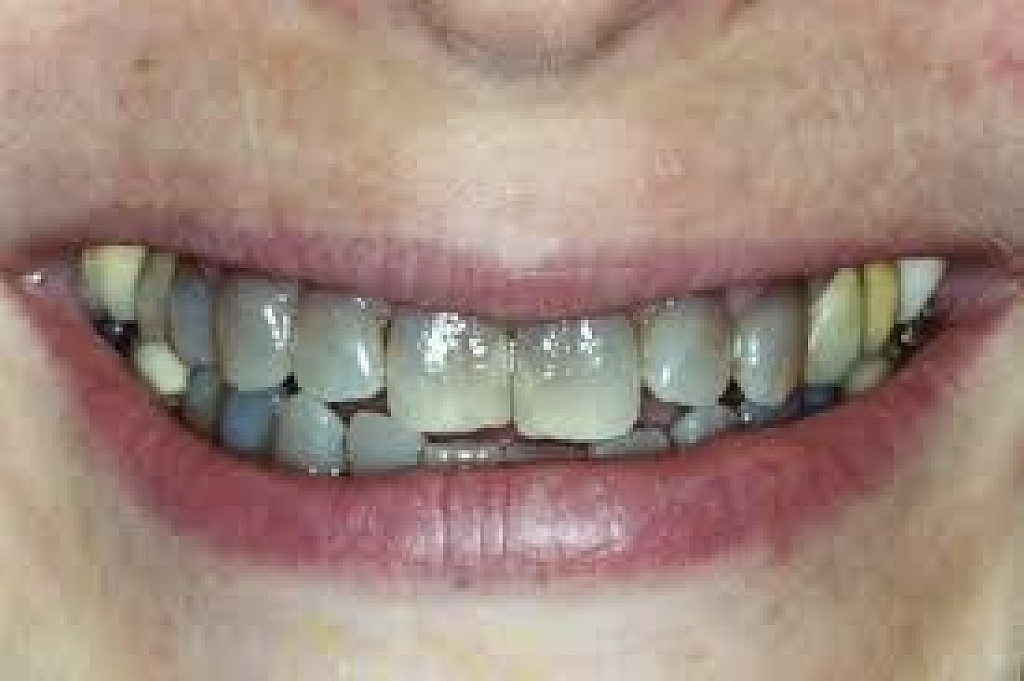

What Causes The Dark Line On My Gums?

You have seen smiles that you know have dental crowns in the front. You look at them and say to yourself that something is not natural. Many times, it is the dark rim of gum tissue that gives it away. The dark rim of gum tissue does not occur around natural teeth, only around teeth that have been covered with dental crowns.

The dark line is associated with an old porcelain dental crown. This style of dental crown is referred to as a porcelain fused-to-metal dental crown because it uses tooth-colored porcelain on the outside and it uses metal under the porcelain for strength. The dark line originates from the edge of the dental crowns where the porcelain and the metal meet at a knife-edge at the gum line. At the knife-edge, a very thin amount of the metal always shows. One of the illusionary techniques cosmetic dentists have used was to hide the thin dark line under the gum line. Over time, the gum tissue would recede and expose the dark line. In some patients the dark line would show through the gum and make it appear dark as well.

How Do You Get Rid of It?

The only way to eliminate the esthetic problem is to replace the dental crowns. When replacing just one single dental crown in the front, you should expect that it might take more than one try-in of the new dental crown before it is permanently cemented into place. Because your central incisors are the most prominent teeth in the mouth, matching them is the most difficult esthetic challenge. Only the best dental technicians are able to mimic one central incisor tooth next to another.

What Are Some of the Replacement Dental Crowns Like?

Some of the clever ways dentists and dental technicians have been able to mimic natural teeth is through the new advancements in dental materials. New all-tooth-colored ceramic dental crowns are the latest technological advancement cosmetic dentists have to recreate natural teeth. In comparison to porcelain fused-to-metal dental crowns, all-ceramic dental crowns do not contain any metal, thus no dark line can appear.

Some advantages and disadvantages of all-ceramic dental crowns are as follows:

Advantages of All-Ceramic Dental Crowns

High esthetics

Excellent fit

If gum recession occurs, there is no dark line

Disadvantages of All-Ceramic Dental Crowns

Not as strong as porcelain-fused-to-metal dental crowns

Cannot be used in all areas of the mouth.